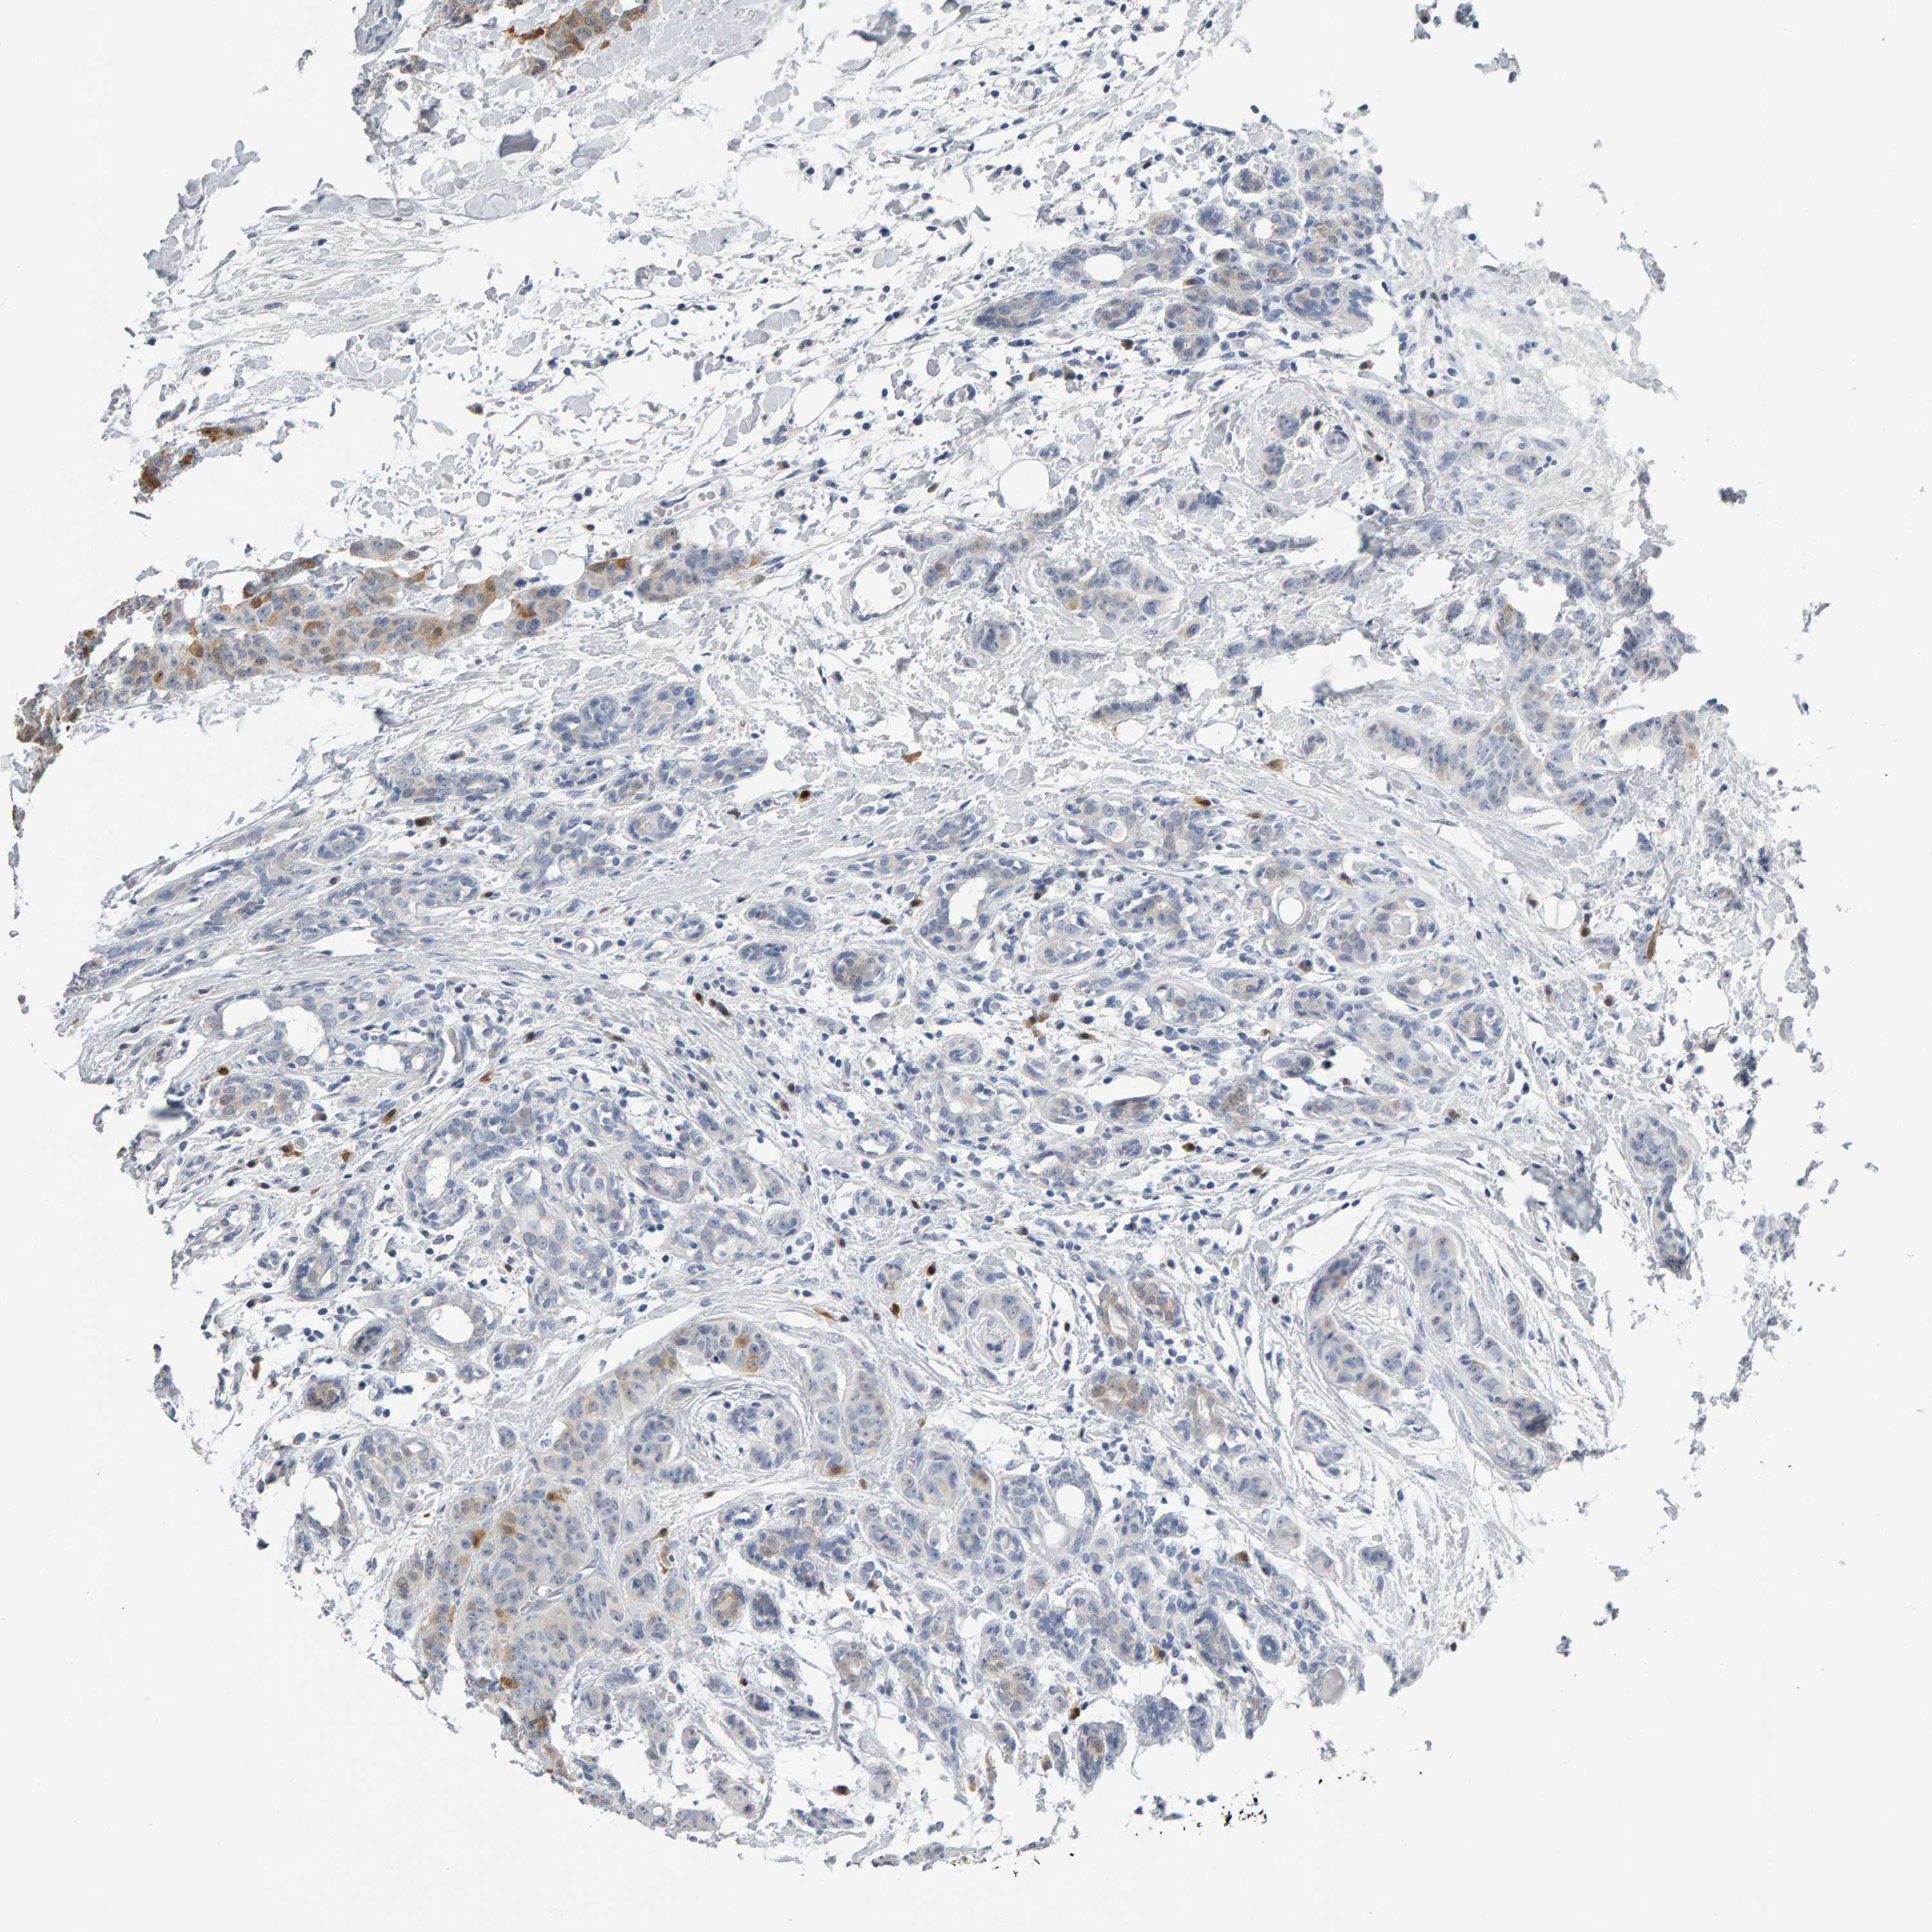

BRCA TCGA BRCA VALIDATION PROTEIN EXPRESSION

ANTIBODIES

AND

VALIDATION